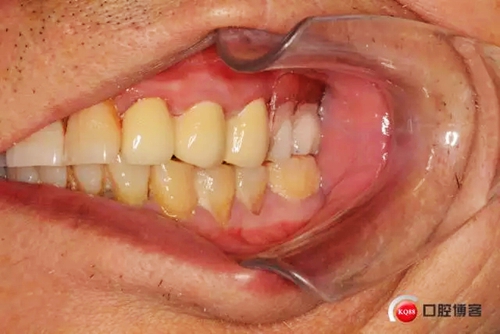

患者初診口腔情況15號牙為原做可摘局部義齒做卡環(huán)預(yù)備,真“專家”的活

口腔檢查:22深齲有瘺管 23 24殘根,15近遠中間隙(機械性片切造成),x片22 23 24 根尖低密度陰影